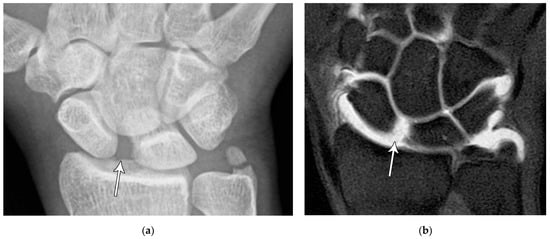

Figure 6. (a) PA radiograph showing a transverse lucent line through the scaphoid waist indicating fracture (arrows), with sclerosis and hypertrophic changes of the fracture margins indicating nonunion with pseudoarthrosis. (b) PA radiograph of the wrist in a different patient showing a more obvious nonunion, again with sclerosis of the fracture margins (arrows) in an untreated injury.